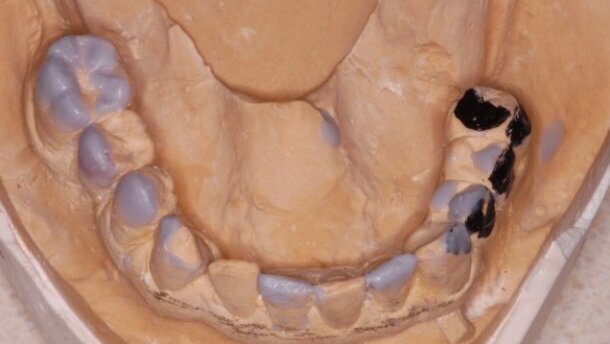

Badanie radiologiczne i kliniczne ujawniło torbiel w prawej zatoce szczękowej, zaniki kostne w wymiarze poziomym i pionowym regionach 14-16, 24-25, 36, 37 oraz 45. Rokowanie zębów #26, #27, #46, #44 określono jako niepewne, jednak nie zostały one zakwalifikowane do ekstrakcji.

Dokonano rejestracji zwarcia przy pomocy łuku twarzowego, wykonano wax-up i przymiarki mock-up’u. Z uwagi na bardzo dużą retruzję zębów 21, 22 oraz 23 zaplanowano protetyczną korektę płaszczyzny licowej zębów. Pacjent odrzucił możliwość leczenia ortodontycznego. Na podstawie rekonstrukcji woskowej przygotowane zostały szablony chirurgiczne.

W oparciu o filary 26, 27 wykonane zostały endokorony protetyczne. Wszystkie pozostałe filary zostały odbudowane pojedynczymi koronami pełnoceramicznymi.

Proces odbudowy protetycznej implantów rozpoczęto pobraniem wycisku w 2 tygodnie po odsłonięciu implantów. Ze względu na jakość kości w regionie 14-16 ostatecznie podjęto decyzję o wykonaniu koron zblokowanych. Wszystkie pozostałe odbudowy na implantach to pojedyncze korony ze stopów metalu licowane porcelaną.